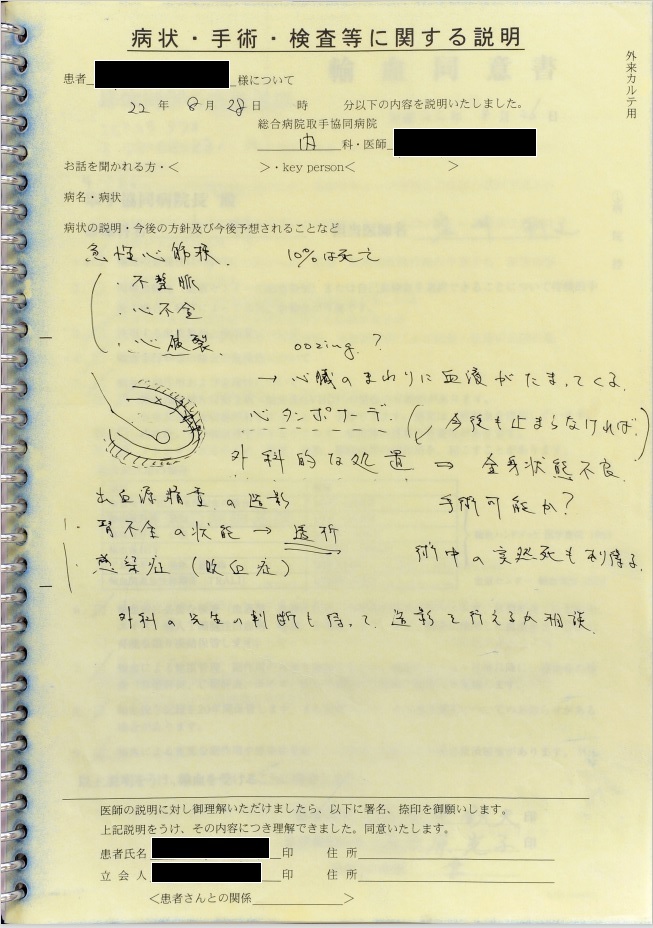

- 8月28日0時過ぎ:「心タンポナーデ」、「心嚢穿刺」の記載

心エコーにて心嚢水増量を認め、血圧50mmHgまで低下したため心嚢穿刺施行、との記載あり。

証拠:カルテ記載・病状説明用紙

8月28日夜半過ぎにショック解除が行われたが、私たち家族への連絡もなく同意も取得していなかった。 私たち家族への着信記録もなかった。 私が心配になり病院に行くと、8月28日午前9時30分の時点で血圧110/60 mmHg, 心拍数100/minとショックから離脱していた。 医師は「夜間、さらに血圧が下がったため、エコーを当ててみると、心嚢水が貯留して心タンポナーデになっていたため、心嚢穿刺を行った」と私に事後報告した。「その原因はoozing型心破裂と言って、心筋梗塞で壊死して脆くなった心筋の隙間から心嚢内に血液が少しずつ漏れ出している状態であり、いずれにしても危険な状態」とのことであった。

このショック解除について、医師は「心嚢穿刺」と説明しカルテにも「心嚢穿刺術」と記載されているが、生命保険診断書には「心嚢穿刺術」の記載がなく、レセプトには「心嚢水」ではなく「胸水」と記載されており、記録間に矛盾がある。心嚢への出血のみで輸血が必要になるほどの貧血になることは考えられず、それよりも大きなスペース(胸腔)への出血が必ず起こっていたと考えられる。実際、「胸水穿刺」と考えると、輸血が必要だったこと、出血性ショックも起こっていた可能性が高いことなどを含め、前後の経過が矛盾なく説明できることから、実際に起こっていた病態は胸腔内への出血に伴う緊張性血胸、出血性ショックで、ショック解除のために行われた手技は胸水穿刺だった可能性が高いと考えられる。